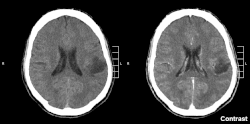

- glejak wielopostaciowy (łac. glioblastoma) – jest najczęstszym (ok. 50%) złośliwym nowotworem wywodzącym się z tkanki glejowej, rosnącym w półkulach mózgu, najczęściej w płacie czołowym i skroniowym. Obraz histopatologiczny urozmaicony, charakterystyczne są duża atypia (złośliwość histologiczna), obszary martwicy i liczne patologiczne naczynia krwionośne, które mogą stać się źródłem wylewu krwi do mózgu. Guz rośnie szybko, często szerzy się poprzez spoidło wielkie na przeciwległą półkulę mózgu (tzw. obraz "motyla" w badaniach obrazowych), może dawać przerzuty w obrębie centralnego układu nerwowego drogą płynu mózgowo-rdzeniowego lub krwionośną. Nowotwór o umiarkowanej promienioczułości. Szczyt zachorowalności to V i VI dekada życia, z niewielką przewagą mężczyzn.

- skąpodrzewiak (łac. oligodendroglioma) – rośnie najczęściej w okolicy płatów czołowych mózgu w istocie białej. Mimo powolnego wzrostu, może we wczesnej fazie rozwoju szerzyć się przez spoidło wielkie na przeciwległą półkulę mózgu (obraz "motyla" w tomografii komputerowej). W późniejszych okresach rozwoju nacieka korę mózgu i oponę pajęczą. Pod względem histologicznym opisywany jest jako przypominający wyglądem "żabi skrzek", z charakterystycznymi mikrozwapnieniami (widocznymi także na radiogramach) i licznymi naczyniami krwionośnymi. Występuje u dorosłych, dwukrotnie częściej u mężczyzn.